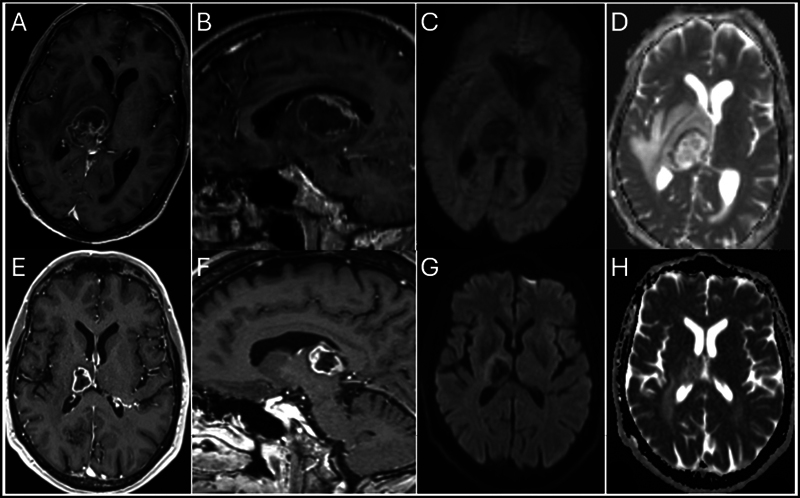

Objectives  Brain abscess is a worrisome condition with a 1-year mortality rate of 21% and a 32% rate of new-onset epilepsy. Brain magnetic resonance imaging (MRI) is strongly recommended as a screening modality with contrast-enhanced T1-weighted images, diffusion-weighted imaging (DWI), and attenuated diffusion coefficient. However, there is a 10% rate of false negative, which could potentially impact management and prognosis. Our systematic review aims at identifying risk factors for false negative. Materials and Methods  A database search of our institutions plus a systematic literature review was conducted using MEDLINE/PubMed, including studies of brain abscesses misdiagnosed as brain tumors. Data on patient demographics, clinical presentations, imaging findings, pathogens, treatments, and outcomes were extracted and analyzed. We present a case of a 59-year-old male with HIV, who developed a brain abscess misdiagnosed as a tumor. Initial symptoms included left-side weakness and weight loss. Imaging showed a ring-enhancing lesion in the right thalamus. The abscess was caused by T. gondii , and the patient was treated with sulfadiazine, pyrimethamine, ceftriaxone, and metronidazole, achieving a GOS-E score of 8 at 1 year. Results  The review included 14 studies, with 1 additional illustrative case, encompassing a total of 15 cases. Patients ranged from 39 to 77 years, with a mean age of 59 years. Comorbidities included human immunodeficiency virus (HIV), glioblastoma, breast cancer, arthritis, gastric cancer, and nephrotic syndrome. Common symptoms were hemiparesis, generalized seizures, headache, and confusion. Imaging often revealed ring-enhancing lesions with restricted diffusion on DWI. Lesions were located in various brain regions. Pathogens identified included 40% Nocardia species, Toxoplasma gondii , Mycobacterium tuberculosis , Aggregatibacter aphrophilus , Rickettsia typhi , Arcanobacterium haemolyticum , Aspergillus terreus , and Providencia rettgeri . Treatments involved antibiotics and, in some cases, surgical intervention. Outcomes measured by the Glasgow Outcome Scale-Extended (GOS-E) at 1 year indicated good recovery in most cases. Conclusion  Despite the high sensitivity and specificity of brain MRI in diagnosing brain abscesses, the standard protocol used for the past two decades still results in a 10% false-negative rate. Such inaccuracies can significantly impact the patient's management, potentially delaying antibiotic therapy and impacting the surgical planning, hence affecting the outcome. Immunocompromised patients are particularly vulnerable to misdiagnoses of brain abscesses as brain tumors. To improve diagnostic accuracy, new imaging techniques and computational tools are currently under investigation.